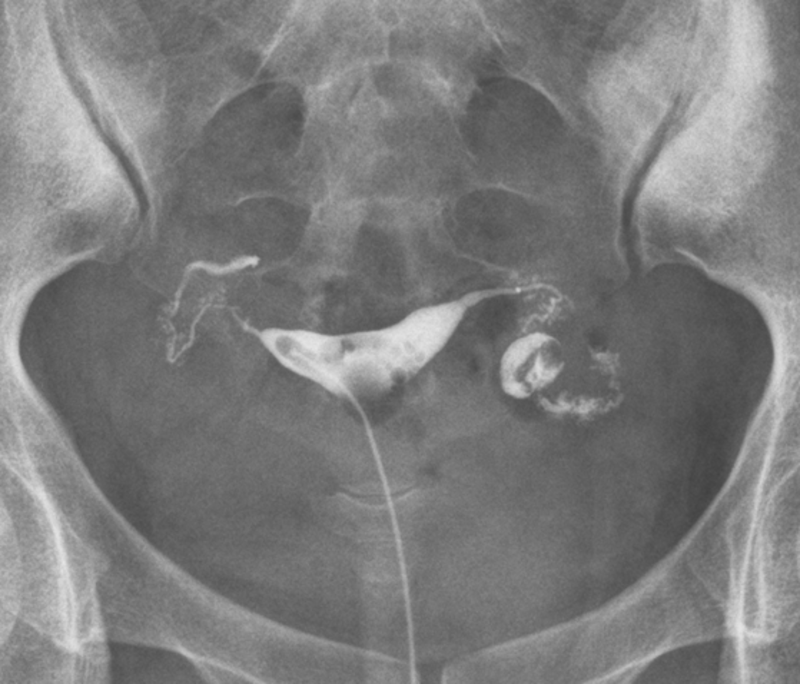

下面是一例(图2、3、4)多次宫外孕,多次腹腔镜手术,最后经我诊断为双侧峡部结节性输卵管炎并右侧输卵管积水,最后腹腔镜行右侧输卵管近段结扎,术后试管婴儿生一健康男婴。

2.png

图2 双侧峡部结节性输卵管炎并右侧输卵管积水